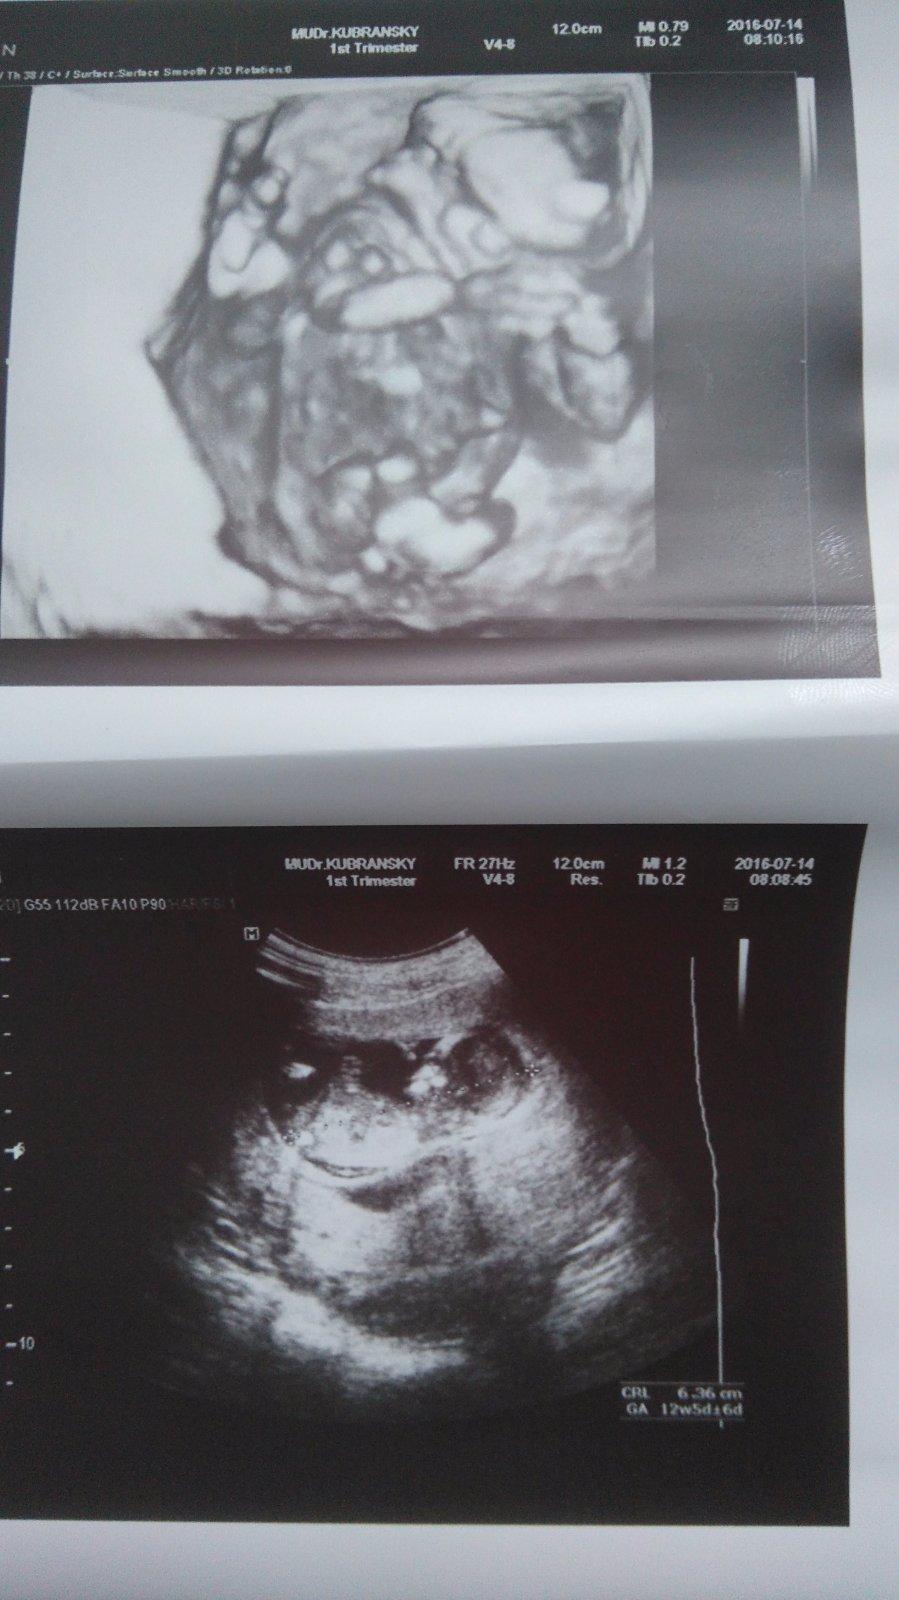

Ahojte..tak dnes som absolvovala 3 D ultrazvuk u Dankovčíka...všetko vyzerá byť v poriadku na 80% ,90% percent to bude dievčatko...zatiaľ sú to vynikajúce správy...ideme ďalej...o týždeň budú výsledky krvi...držím všetkým maminám prsty...🙂)

@sandri sama som bola prekvapená...sama sa ma opýtala ..chcete vedieť pohlavie a ja že no ak vidíte niečo tak samozrejme ...a tak povedala, že na 80 až 90% percent dievčatko...že je tam uhol 8 stupnov...do 30 je vraj dievča nad 30 je chlapec...nejaký uhol od hrbolčeka alebo tak nejako som to čítala niekde..neviem už presne...beriem to s rezervou...ale trošku sa teším..lebo som aj chcela druhé dievčatko...tak uvidíme...nakoľko je to pravda...🙂)

Ahojte baby 🙂 uz mam po poradni 🙂 dopadla super 🙂 vsetko v poriadku . babo o trosku mensie ale ze to je v pohode 🙂 ved velke nechcem kto by to porodil potom 😂 mam aj dve fotky 🙂 dalsia poradna 8.8 🙂 malinke sa riadne vrtelo 🙂 tesime sa 🙂 predpokladany termin 23.1. 🙂